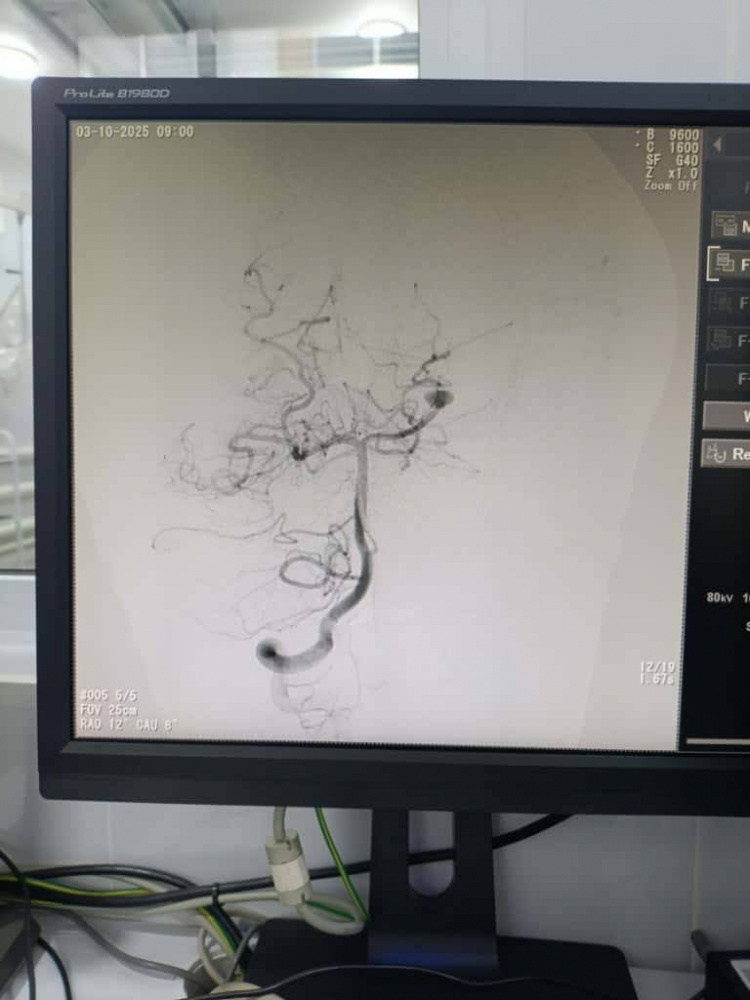

Нейрохирурги Национального центра охраны материнства и детства совместно с коллегами из Национального госпиталя провели несколько высокотехнологичных эндоваскулярных операций детям с тяжелыми сосудистыми заболеваниями головного мозга — аневризмами и артериовенозными мальформациями.

На дооперационном этапе выполнялась ангиографическая диагностика, позволившая определить размеры и расположение сосудистых аномалий и выбрать оптимальную эндоваскулярную тактику для каждого пациента.

При лечении аневризм выполнялась эндоваскулярная окклюзия с сохранением проходимости магистральных сосудов, а при артериовенозных мальформациях — точечная эмболизация патологического узла для предотвращения риска кровоизлияния. Все манипуляции осуществлялись под контролем цифровой субтракционной ангиографии.

После операций проведена контрольная ангиографическая оценка, подтвердившая успешное выключение патологических очагов из кровотока и отсутствие осложнений. Все дети благополучно вышли из наркоза и переведены в отделение реанимации для наблюдения. По данным врачей, состояние пациентов стабильное, осложнений не отмечено, восстановление проходит активно.